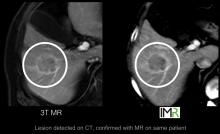

The introduction of new technology into the magnetic resonance imaging (MRI) landscape has changed the face of the market segment over the last year. Although MRI satisfaction scores tend to cluster together, the differences are in the details, according to recent findings from healthcare technology research firm KLAS in its report MRI 2012: Broadening Your Field of View.